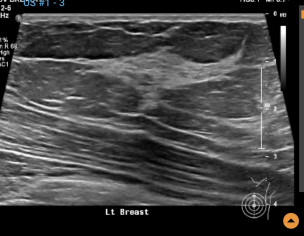

Left breast ultrasound report said no concerns. Symptoms - enlarged lymph nodes left breast, small cyst, changes in size and shape of left breast, dimples in lower left breast, pain in outer quadrant of left breast. Second opinion on ultrasound pics?